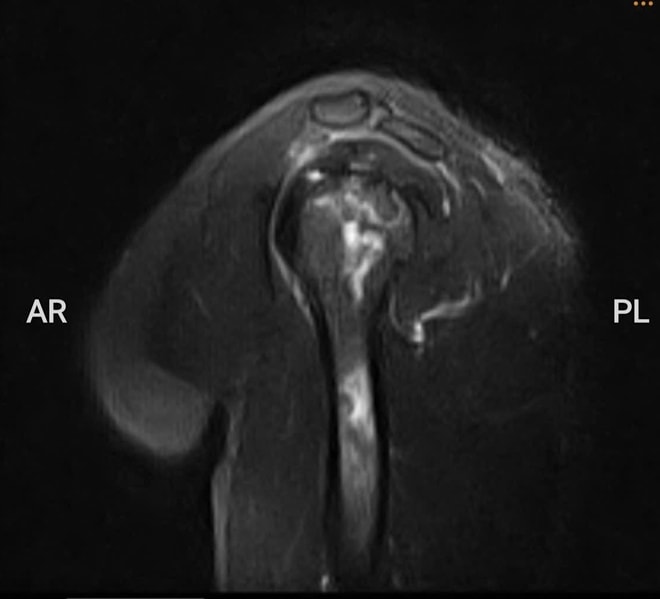

Hình ảnh chụp MRI cho thấy bệnh nhân bị hoại tử chỏm xương cánh tay trái, ổ hoại tử lan xuống vùng cổ và thân xương cánh tay.

Kết quả chụp MRI cho thấy phần chỏm xương cánh tay trái bị hoại tử, ổ hoại tử lan xuống vùng cổ và thân xương cánh tay. Khi chụp X-quang phần khớp háng nhận thấy dấu hiệu hoại tử vô mạch chỏm xương đùi hai bên độ 2 theo ficat và alert (tình trạng tế bào xương ở chỏm xương đùi chết đi do mất nguồn cung cấp máu).